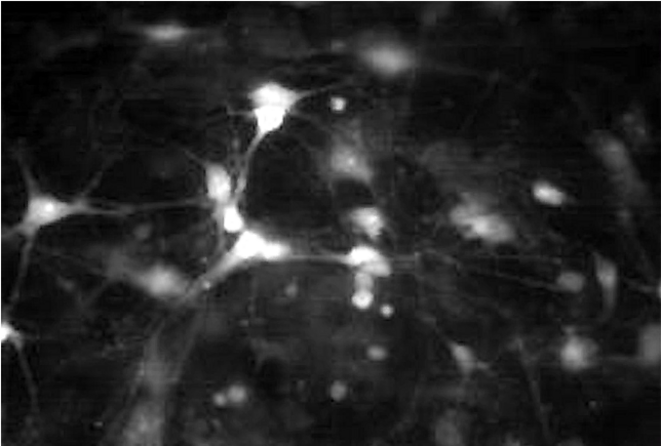

Les organoïdes cérébraux - des nœuds de tissu neuronal cultivés à partir de cellules souches - ont montré un nouveau potentiel pour imiter les conditions liées à l'autisme